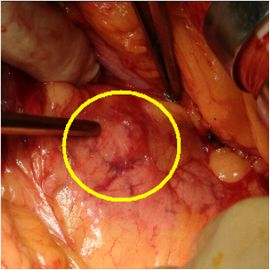

CT検査にて膵体部に腫瘍を認め、精査の結果、膵体部腫瘍疑いと診断し膵体尾部切除術を施行した。

病理診断結果はインスリノーマ(インスリン産生膵島細胞腫)であった。

手術画像